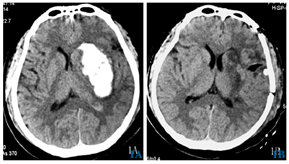

开颅血肿清除术术前术后对比